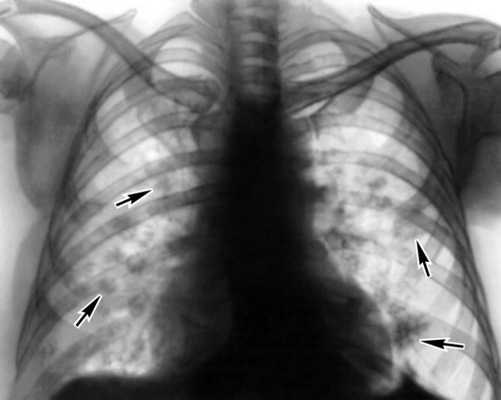

Диагноз парагонимоза подтверждается обнаружением овальных золотисто-коричневых яиц паразита в мокроте и кале больного. В первые 2-3 месяца после заражения более информативны серологические методы (ИФА), выявляющие специфические антитела к антигенам гельминта. В крови при парагонимозе определяется эозинофилия, лимфоцитоз, гипохромная анемия. На рентгенограмме легких парагонимозные кисты представлены в виде размытых кольцевидных затемнений с ровными гладкими границами в одном или нескольких легочных сегментах. При рентгенографии черепа видны кальцификаты в форме «мыльных пузырей». При лапароскопии в брюшной полости обнаруживается выпот геморрагического, фибринозного или фибринозно-гнойного характера, в котором можно выявить незрелых гельминтов. Дифференциальная диагностика осуществляется в отношении туберкулеза, пневмонии, эхинококкоза и новообразований легких, при поражении мозга - опухолей мозга, менингита.

Диагноз основывается на данных клин, и рентгенол, обследования больного и на результатах исследования мокроты и кала на яйца парагонимуса. Рентгенологически в легких обнаруживают инфильтративные изменения, кольцевидные тени (кисты), очаговые изменения и пневмосклероз, в ряде случаев с обызвествлениями. В первые 3 мес. после заражения, когда паразиты еще не достигли половой зрелости, яйца не обнаруживают. В этот период для диагностики применяют внутрикожную аллергическую пробу и серол, реакции, к-рые становятся положительными уже через 2—3 нед. после заражения.

Инструментальная диагностика заболевания базируется на рентгенографии легких. Она может указать на инфильтраты воспалительного характера, плеврит, спаечный процесс, кистозные образования с нечеткими границами в полости органа.

В хронической фазе развивается очаговый фиброз лёгких; рентгенологически выявляют очаги затемнения с просветлениями в центре. Возможны диффузный пневмосклероз, легочное сердце, легочное кровотечение, рак легких. Занос паразитов в мозг приводит к энцефалиту и менингоэнцефалиту, объемному процессу, напоминающему опухоль. При диссеминации яиц возможен полисерозит.

В хронической фазе развивается очаговый фиброз легких; рентгенологически выявляют очаги затемнения с просветлениями в центре. Возможны диффузный пневмосклероз, легочное сердце, легочное кровотечение, рак легких. Занос паразитов в мозг приводит к энцефалиту и менингоэнцефалиту, объемному процессу, напоминающему опухоль. При диссеминации яиц возможен полисерозит.